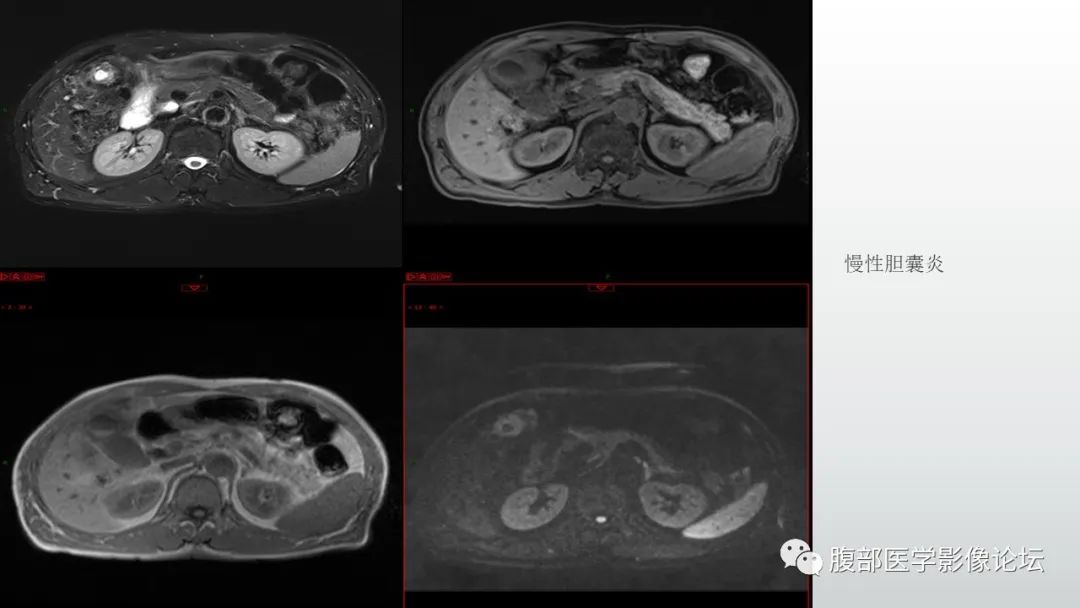

【病例】胆囊管状腺瘤1例CT及MR影像表现-1